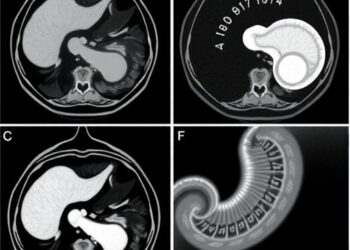

MR Enterography Reveals Hepatobiliary Insights in Pediatric IBD

In a groundbreaking study set to reshape the understanding of inflammatory bowel disease (IBD) in pediatric patients, researchers have identified ...